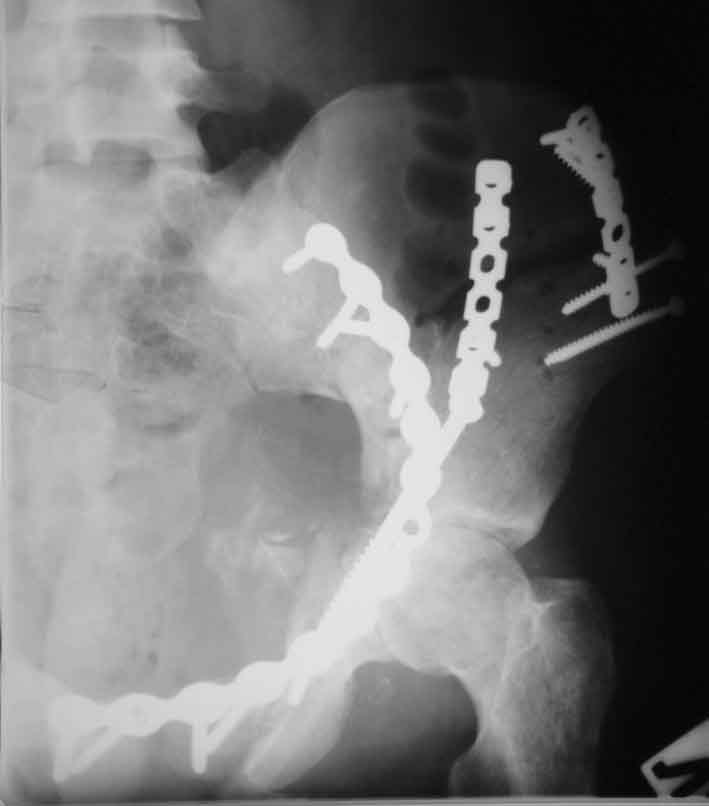

Рентгенограмма до операции

Перелом. Внутритазовый обзор.